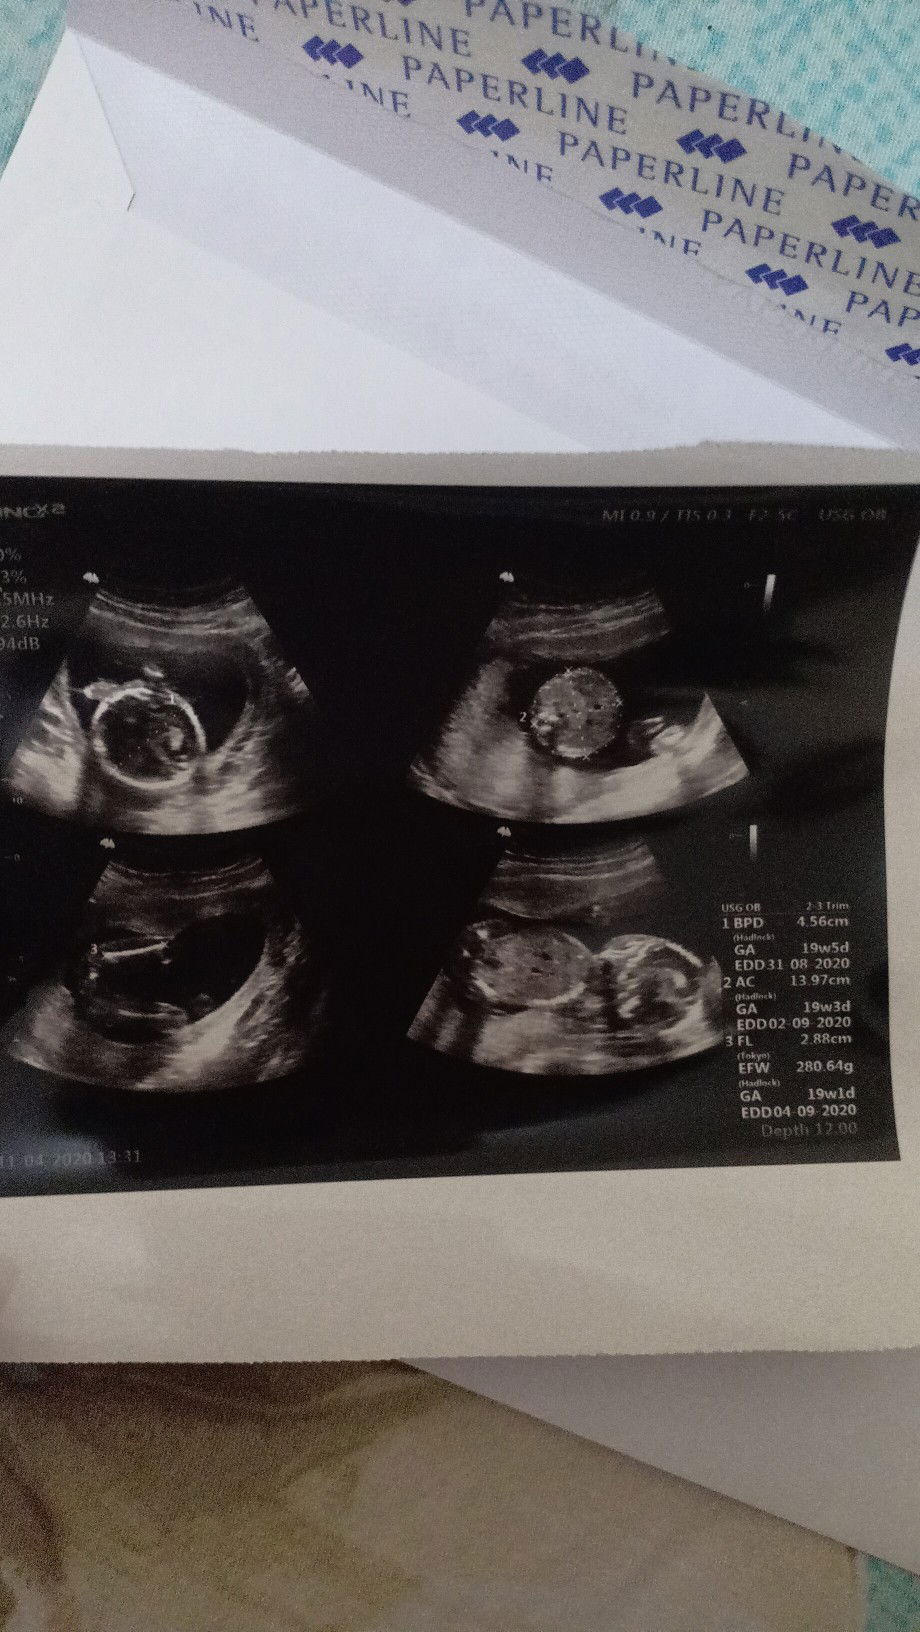

Banyak yaaa... saya dr awal hamil smpek 19wk br naik 1 kg. Saya g mual muntah dll. Normal makannya bahkan sering laper dan makan nasi. Tp aku imbangin sma kurma dan madu asli.